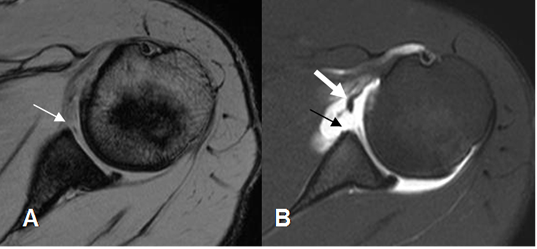

Fig 63. Lesión de Bankart.

A: RM axial en FFE y B: ArtroRM axial. Signos de lesión de Bankart, que se confirma en la ArtroRM. (Flecha delgada). Adicionalmente hay ruptura del LGH medio. (Flecha gruesa).